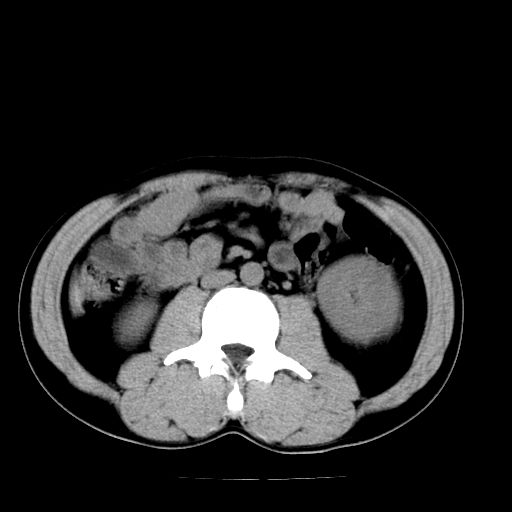

以下是引用天南地北在2007-4-30 13:36:00的发言:[br]支持慢性胰腺炎伴有假性囊肿

以下是引用andymaomao在2007-4-30 14:28:00的发言:[br]支持:1.慢性胰腺炎并假性囊肿形成可能;[br] 2.左肾形态稍增大,旋转不良。